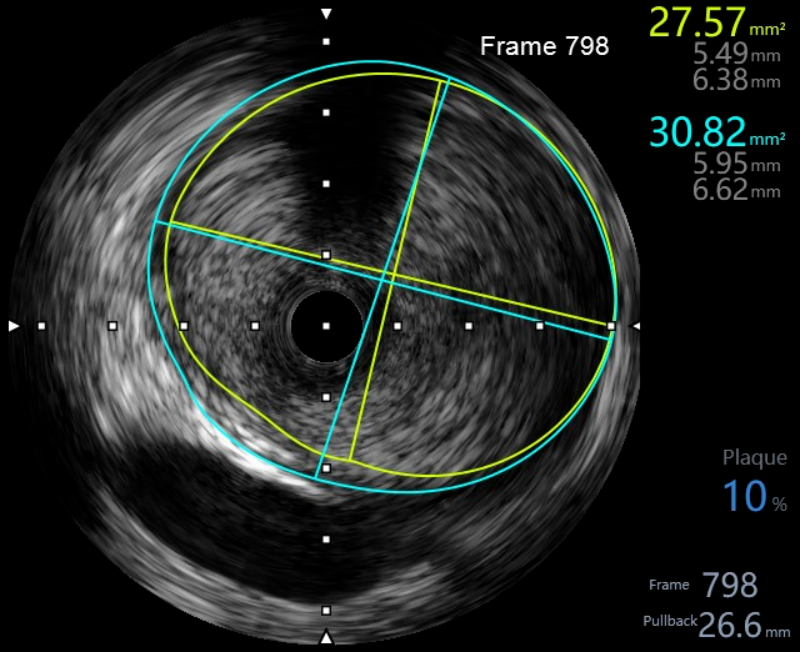

在惠州市中心人民医院派驻中文博彩平台分院专家、中文博彩平台分院心血管内科谢桂庭主任和谢志恒科副主任的带领下,成功开展了中文博彩平台分院第一例冠状动脉血管内超声(IVUS)检查。术中行冠状动脉血管内超声(IVUS)检查:回旋支中段瘤样扩张,少量血栓影,最大管腔直径约6mm,未见夹层、血肿(图4、5)。患者病变为冠脉瘤样扩张并血栓形成,予抗栓等治疗后患者好转出院。

(图4)

(图5)